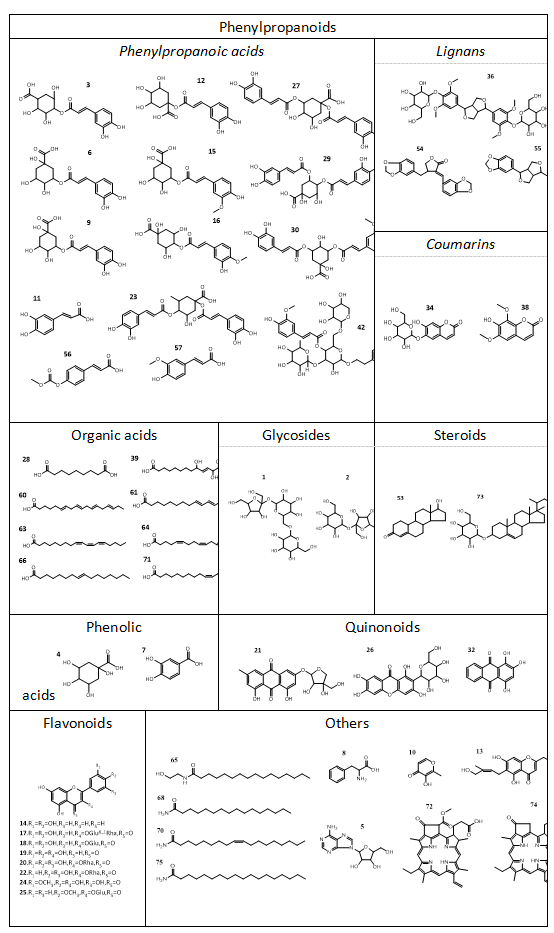

针对这一需求,刘金平教授团队采用UPLC-Q/TOF-MS结合UNIFI平台,系统解析了两种叶片的化学成分相似性,从中共鉴定出75种化学成分,其中69种为共有成分(图1)。另外分别有12种和32种化合物首次从SCL与SFL中被鉴定出来,这些发现为两种五加叶的化学表征及药效物质基础研究提供了重要依据。

图1 SCL和SFL中化学成分的化学结构